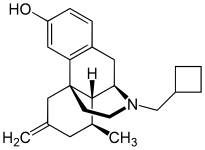

Others

- Butorphanol

- Nalbuphine

Structures

| Other Morphinans | ||||

Butorphanol Butorphanol |